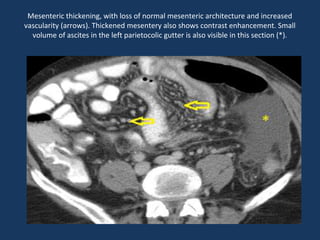

Mesenteric thickening, with loss of normal mesenteric architecture and increased

vascularity (arrows). Thickened mesentery also shows contrast enhancement. Small

volume of ascites in the left parietocolic gutter is also visible in this section (*).

Mesenteric thickening, withloss of normal mesenteric architecture and increased vascularity (arrows). Thickened mesentery also shows contrast enhancement. Small volume of ascites in the left parietocolic gutter is also visible in this section (*).